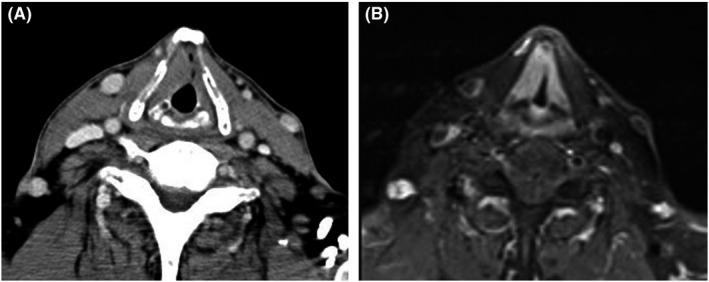

In clinical practice, it is sometimes difficult to evaluate the intra-false vocal fold lesion. Transcutaneous ultrasound can be an option to evaluate the soft tissue lesion within the right false vocal cord in a 65-year-old man with laryngeal Rosai-Dorfman disease presenting with hoarseness and right false cord swelling.

在临床实践中,有时难以评估假声带内的病变。对于一名65岁患有喉Rosai-Dorfman病且表现为声音嘶哑和右侧假声带肿胀的男性患者,经皮超声可作为评估右侧假声带内软组织病变的一种选择。